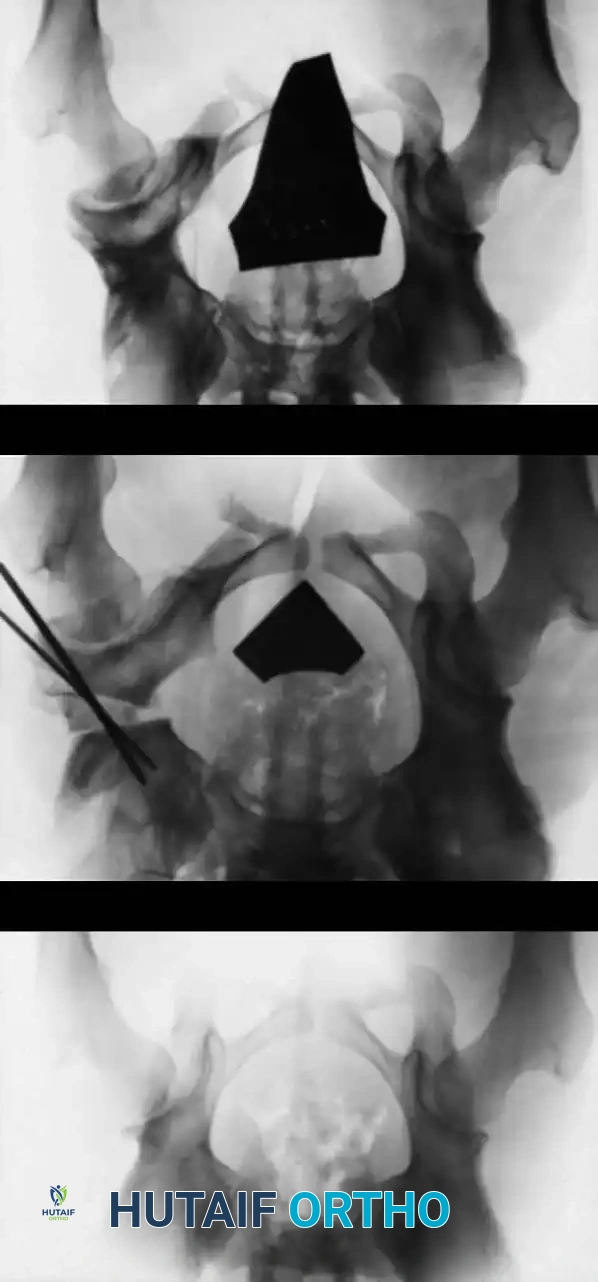

3. Arthrogram: Dye is injected to visualize the cartilaginous profile. Look for the "rose thorn" sign (limbus), the transverse acetabular ligament, and the ligamentum teres. Pooling of dye medially indicates an interposed pulvinar or inverted limbus preventing concentric reduction.

Intraoperative arthrogram demonstrating the cartilaginous contours of the femoral head and acetabulum during closed reduction.

Radiographic appearance following a complex pelvic osteotomy with internal fixation, demonstrating improved center-edge angle and acetabular coverage.